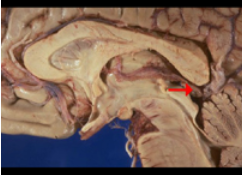

如图箭头所示为大脑哪个部位( )

A:中脑顶盖

B:后连合

C:四叠体

D:松果体

E:中脑导水管